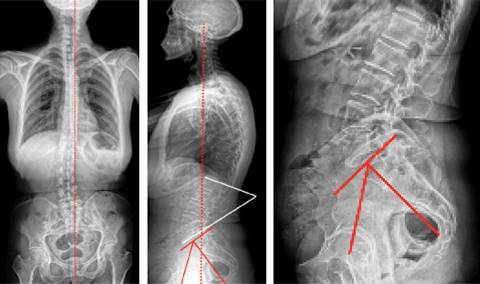

Aunque se han hecho esfuerzos para caracterizar el centro de gravedad del cuerpo humano y en consecuencia su equilibrio sagital, esta caracterización está fuertemente afectada por la postura, la posición corporal y por las alteraciones anatómicas congénitas y/o adquiridas. Por lo tanto, no es posible universalizar un somatotipo postural único en la especie humana (Figuras 6 y 7); en otras palabras, la morfología de la postura sagital varía de persona a persona y es específica para cada individuo.25,26

Figura 6: En la Figura de la izquierda se muestra un equilibrio sagital adecuado. A la derecha observe cómo se modifica el equilibrio según la inclinación pélvica ocasionada por trastornos posturales.

Figura 7: En las Figuras se muestra cómo se puede afectar el equilibrio sagital y la inclinación pélvica según la posición adoptada por un individuo.